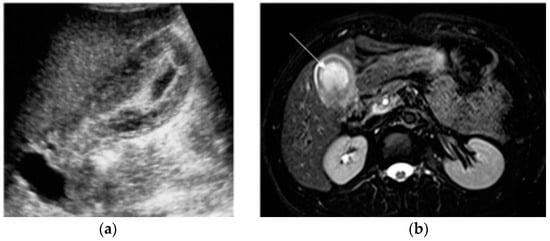

Most ovarian masses diagnosed in pregnancy are benign and are spontaneously resolved (Figure 9). Surgical management is warranted when masses are suspicious for malignancy, at risk for torsion or clinically symptomatic [3].

Figure 9.

Left adnexal torsion in 28-year-old patient at 35 weeks of gestation. Axial (a) and coronal (b) T2-weighted images show left cystic formation of about 8 cm (arrow) that has undergone torsion, compressed between the gravid uterus and the abdominal wall.